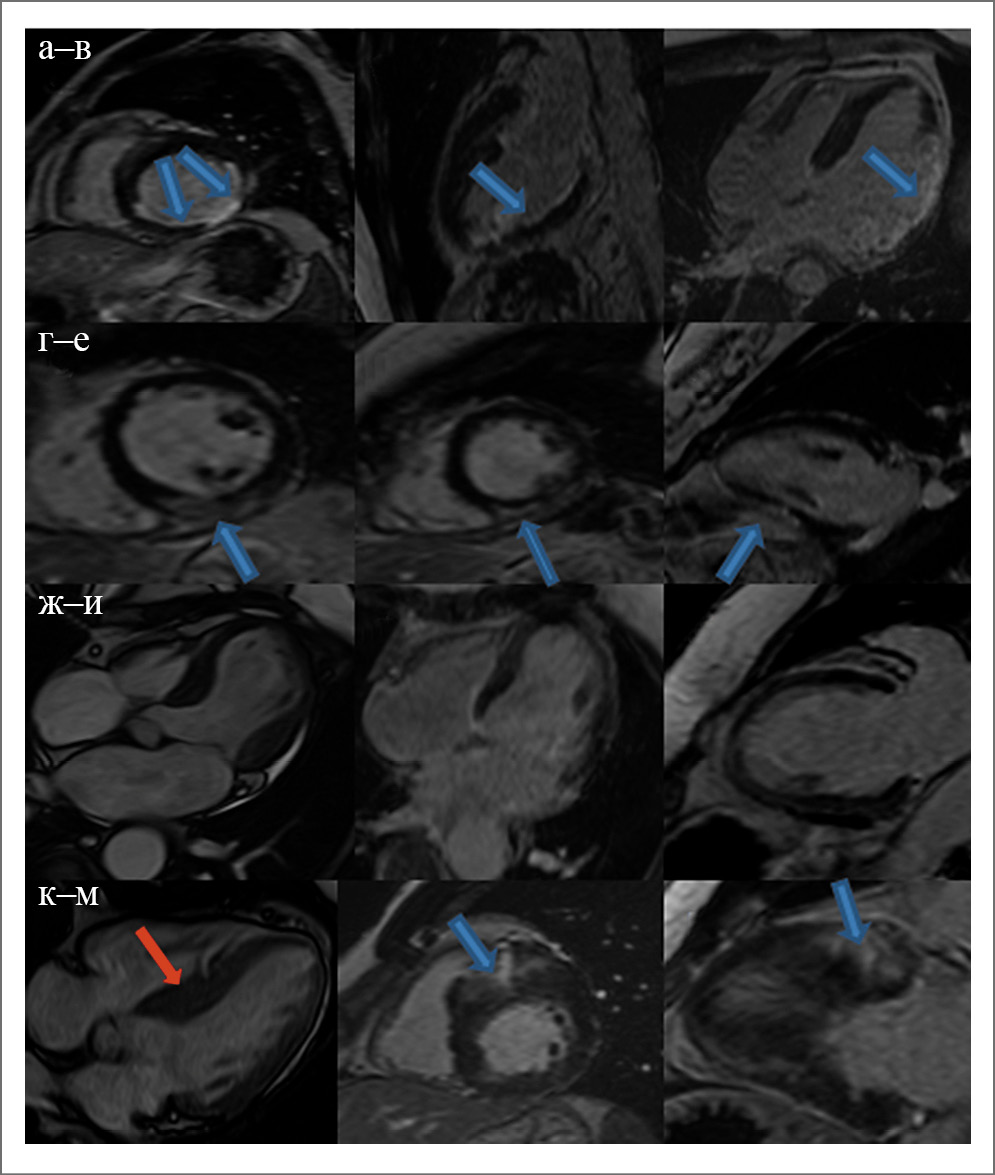

Рис. 1. МРТ пациентов из 4 представленных групп: а–в – ИМ, субэндокардиальное накопление контрастного препарата в нижней и латеральной стенке (стрелка); г–е – миокардит, субэпикардиальное накопление контрастного препарата в нижней стенке (стрелка); ж–и – синдром такоцубо, баллонирование верхушки на кино-изображениях (левое изображение) и отсутствие отсроченного контрастирования миокарда (центральное и правое изображения); к–м – ГКМП, асимметричное утолщение межжелудочковой перегородки (красная стрелка), фокальное интрамиокардиальное накопление контрастного препарата в наиболее гипертрофированном базальном переднеперегородочном сегменте миокарда ЛЖ.